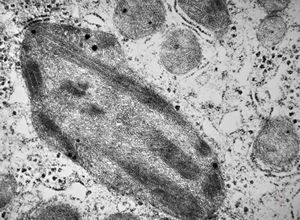

M,1y. | unusually cup-shaped mitochondria - plexus papilloma

M,1y. | intramitochondrial inclusion - plexus papilloma